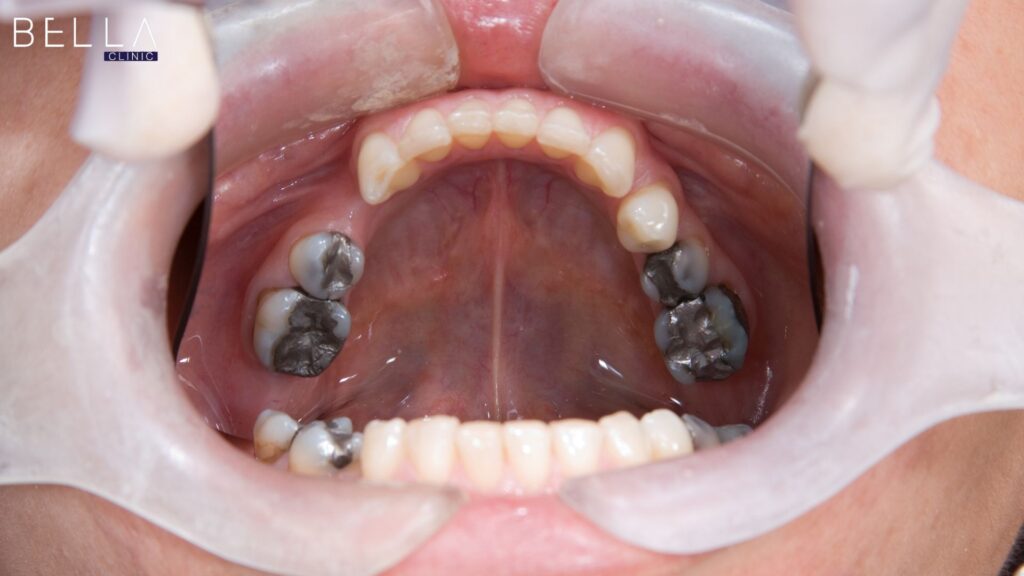

بالإضافة إلى ذلك، تفشل الحشوات التجميلية البسيطة غالباً في علاج المشاكل المعقدة بشكل مستهدف وفعال تماماً. بناءً على ذلك، يقدم التدخل الطبي دفعة قوية وضرورية لتغيير مظهرك الخارجي بالكامل وإبراز نضارتك الدفينة.

من الناحية العملية، يعالج الإجراء الطبي مشكلة صعوبة مضغ الطعام أو ضعف النطق بفاعلية قصوى ومباشرة. بالتالي، تستعيد قدرتك الوظيفية المتناسقة بسهولة شديدة بفضل تقنيات التركيب المتطورة طبياً داخل العيادات المتخصصة.

من ناحية أخرى، تعالج هذه الخطوة حالات كسر وضعف المينا المرتبطة بالتسوس العميق بفاعلية وأمان لتجنب المضاعفات. نتيجة لذلك، يحسن التدخل الطبي مظهر الثلث السفلي للوجه ويزيد من راحتك النفسية بشكل جذري وملحوظ جداً.

بالتالي، يستخدم طبيب الأسنان القشور الخزفية الرقيقة دون القدرة على حماية العظم السفلي المتهالك إطلاقاً. بالمقابل، تركز العمليات الخاصة بالترميم الشامل على تعويض الأسنان المفقودة بالكامل بمهارة فنية عالية ومستدامة للأبد.

نتيجة لذلك، يعالج الطبيب جذور الأسنان التالفة ويرسم خطوطاً بوضوح تام لتثبيت الزرعات للمريض. هكذا، يحصل المريض على وظيفة مضغ قوية ويحافظ على مسافات الفك الطبيعية من الخلل المستمر.

التركيبات الخزفية وجماليات الأسنان

ثالثاً، يفضل بعض الأطباء استخدام التركيبات الخزفية الكاملة للحالات التي تتطلب قوة استثنائية وتجميلاً مثالياً. يبرد الطبيب السن التالف ويركب الغطاء الزيركوني بمهارة فائقة لتعويض الجزء المفقود بالكامل وبأمان تام.

علاوة على ذلك، يضمن هذا التدخل السريع التخلص من الفراغات المزعجة بشكل نهائي ومستقر للمريض تماماً. هكذا يحقق المريض تحولاً جذرياً وشاملاً يعيد له قدرة المضغ بقوة ووضوح ومظهر طبيعي.